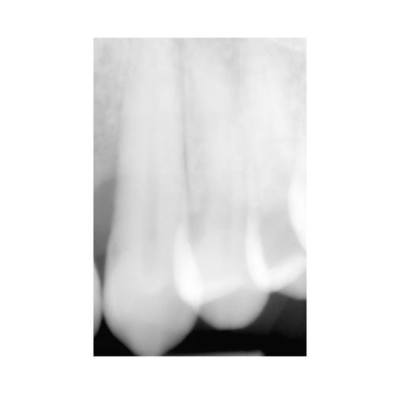

PARODONTOLOGIA - SEDAZIONE E LASER TERAPIA

Lo Studio dentistico Oleggini di Busto Arsizio, nell’ampio inventario di servizi prestati prevede anche la parodontologia, la sedazione cosciente dei pazienti e la laser terapia.